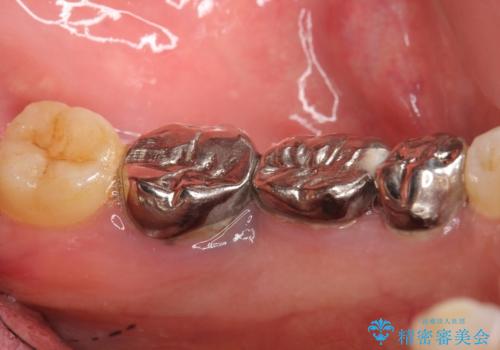

保存不可能な奥歯(左下6)を抜歯し、機能していない親知らず(左下8)の移植を行いました。

移植後、生着を待って根管治療及び補綴修復を行いました。